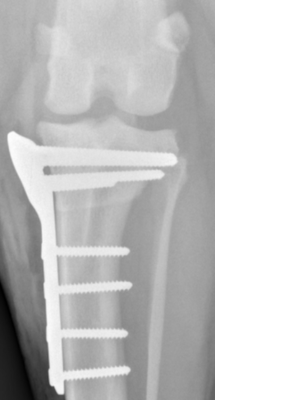

Concrètement, le chirurgien réalise une ostéotomie circulaire du tibia proximal, puis fait pivoter le plateau tibial afin de réduire son angle. Cette modification neutralise la « poussée tibiale craniale » qui, lors de l’appui, provoquait le glissement anormal du tibia sous le fémur. L’os est ensuite stabilisé à l’aide d’une plaque spécifique et de vis, généralement laissées en place à vie si elles ne provoquent aucune gêne.